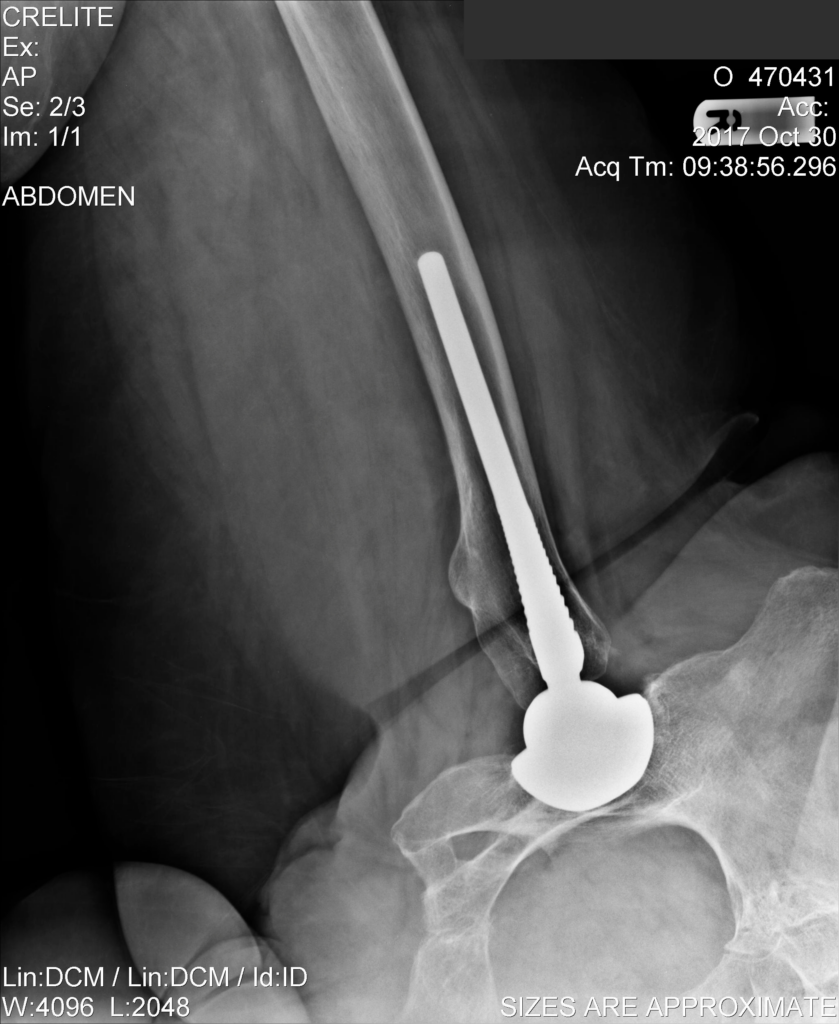

Ακτινογραφίες ασθενή ΜΕΤΑ από επέμβαση αμφοτερόπλευρης αρθροπλαστικής ισχίων που πραγματοποιήθηκε προ 10ετίας